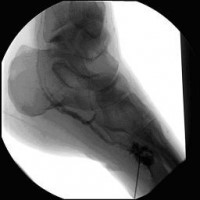

Perkutane Embolisation einer low-flow venösen Malformation (Gefäßmissbildung) der Fußsohle-1

(Bild 4 von 5)